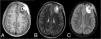

An 11-year-old boy presented with increased volume in the left frontal region, without neurological deficit or systemic symptoms. CT and MRI revealed an aggressive osteolytic lesion with perilesional oedema and intracranial extension.

Un niño de 11 años presentó aumento de volumen en la región frontal izquierda, sin déficit neurológico ni síntomas sistémicos. La tomografía y la resonancia magnética revelaron una lesión osteolítica agresiva con edema perilesional y extensión intracraneal.